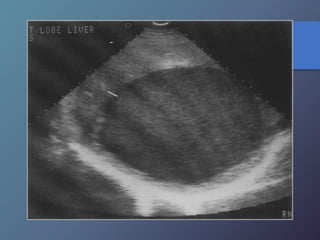

Traumatismo Hepático

• La lesión hepática es a predominio del lóbulo derecho.

• Mayor particularidad en segmento posterior.

• Mayor frecuencia por laceración peri vascular.

• Se producen hematomas subcapsulares,

pericapsulares o aislados.

• La hemorragia en las primeras 24 horas es ecogénica y

posteriormente se hace mas hipoecogénica.

• Entre las dos o tres semanas se puede observar gran

cantidad tejido de granulación.